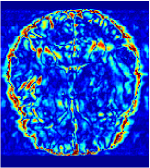

All the experiments are implemented on a Windows workstation with Intel Core i9 CPU at 3.3GHz and an Nvidia GTX-1080Ti GPU with 11GB of graphics card memory via TensorFlow Abadi et al. (2016). The parameters in the proposed network are initialized by using Xavier initialization Glorot and Bengio (2010). We trained the meta-learning network with four tasks synergistically associated with four different CS ratios: 10%, 20%, 30%, and 40%, and test the well-trained model on the testing dataset with the same masks of these four ratios. We have 300 training data for each CS ratio, which amount to total of 1200 images in the training dataset. The results for and MR reconstructions are shown in Tables 5.4 and 5.4 respectively. The associated reconstructed images are displayed in Figures 1 and 3. We also test the well-trained meta-learning model on unseen tasks with radio masks for skewed ratios: 15%, 25%, 35%, and random Cartesian masks with ratios 10%, 20%, 30% and 40%. The task-specific parameter for the unseen tasks are retrained for different masks with different sampling ratios individually with fixed task-invariant parameters . In this experiments, we only need to learn for three skewed CS ratios with radio mask and four regular CS ratios with Cartesian masks. The experimental training proceed on less data and iterations, where we performed on 100 MR images with 50 epochs. For example, for reconstructing MR images with CS ratio 15% radio mask, we fix the parameter and retrain the task-specific parameter on 100 raw data with 50 epochs, then test with renewed on our testing data set with raw measurement that sampled from radio mask with CS ratio 15%. The results associated with radio masks are shown in Table 5.4 and 5.4, Figure 2 and 4 for and images respectively. The results associated with Cartesian masks are list in Table 5.4 and reconstructed images are displayed in Figure 5.

In general supervised learning, training data need to be in the same or similar distribution, heterogeneous data exhibits different structure variations of features which hinders CNNs to extract features efficiently. In our experiments, raw measurements sampled from different ratios of compressed sensing display different levels of incompleteness, these undersampled measurements do not fall in the same distribution but they are related. Different sampling masks are shown at the bottom of Figure 1 and 2 may have complemented sampled points, in the sense that some of the points which sampling ratio mask does not sample have been captured by other masks. In our experiment, different sampling masks provide their own information from their sampled points so that four reconstruction tasks help each other to achieve an efficient performance. Therefore, it explains the reason that Meta-learning is still superior to conventional learning when the sampling ratio is large.

Qualitative comparison between conventional and Meta-learning methods are shown in Figure 1 and 3, which display the reconstructed MR images of the same slice for T1 and T2 respectively, we label the zoomed-in details of HGG in the red boxes. We observe the evidence that conventional learning is more blurry and lost sharp edges, especially in lower CS ratios. From the point-wise error map, we find meta-learning has the ability to reduce noises especially in some detailed and complicated regions comparing to conventional learning.